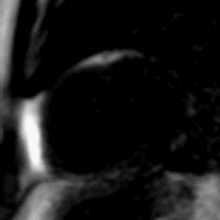

تخلیه وریدی ریوی غیرعادی جزئی توسط CMR